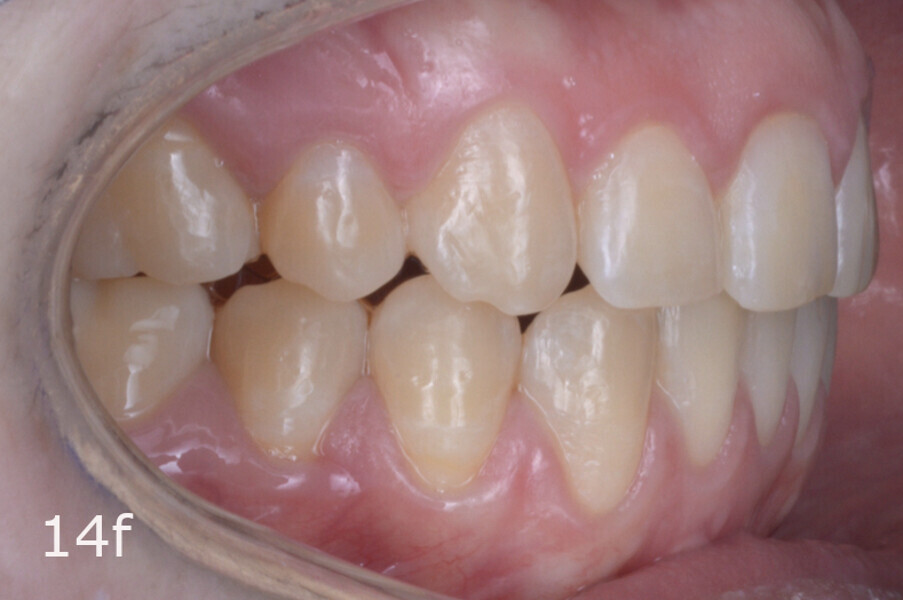

The 23-year-old dolichofacial female patient complained of not being able to chew properly. Facial examination showed a convex profile, an enlarged lower facial height, and a skeletal Class III malocclusion (Figs. 1–3). Intra-oral examination revealed an Angle Class III right subdivision malocclusion, anterior open bite, no overjet and a maxillary dental midline deviated about 3 mm to the right compared with the mandibular dental midline (Fig. 4). The panoramic radiograph confirmed previous extraction of the maxillary right first premolar and the presence of all four third molars (Figs. 5 & 6).

The treatment objectives included closing the anterior open bite, achieving a bilateral Angle Class I relationship and a proper overjet and overbite, correcting the midline discrepancies, and achieving a profile harmonisation. The treatment plan consisted of orthodontic camouflage treatment with asymmetric distalisation in three of the four quadrants using Invisalign aligners (Align Technology) and third molar extraction. The Invisalign Comprehensive package was chosen, and 63 pairs of aligners were used (Figs. 7–10). Each aligner was worn for 20 hours a day for one week each. The use of Class III elastics on both sides was indicated. Afterwards, ten refinement aligners were needed to improve the interdigitation on the right side (Figs. 11 & 12).

The total treatment time was 15 months. An Angle Class I relationship was established along with adequate anterior and canine guidance, establishing a functional occlusion. This not only ensures optimal masticatory function but also protects the teeth and the temporomandibular joint from excessive force. Maxillary and mandibular fixed retention were installed at the end of the treatment (Figs. 13–19).